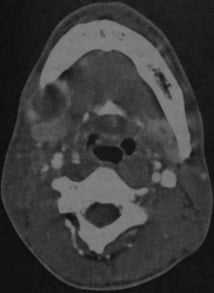

КТ с контрастированием: абсцесс дна полости рта справа с распространением под нижнюю челюсть. Абсцесс примыкает с правой стороны к телу нижней челюсти, определяется как образование со сниженной плотностью в центре, окруженное усиленной стенкой. Поднижнечелюстная железа смещена кзади (стенка абсцесса интактна, инфильтрация в данном случае отсутствует).

Абсцесс дна полости рта, расположенный справа около средней линии. КТ с контрастированием: объемное образование с типичным снижением плотности в центре, окруженное усиленной стенкой. Мелкий абсцесс слева, примыкающий к нервно- сосудистому пучку, с сопутствующим отеком поднижнечелюстных мягких тканей.

КТ с контрастированием: левосторонний паратонзиллярный абсцесс. Образование имеет гипоинтенсивный центр, окруженный усиленной стенкой. Отек левой нёбной миндалины и слизистой глотки на стороне поражения вызывает асимметричное сужение глотки. Рот остается открытым в связи с болевым синдромом.

КТ с контрастированием (реконструкция во фронтальной плоскости): левосторонний паратонзиллярный абсцесс. Выявляется перифокальный отек и повышенная плотность слизистой, а также асимметричное сужение ротоглотки, распространяющееся в дистальном направлении слева от мягкого нёба. В абсцессе наблюдается типичное периферическое усиление с гипоинтенсивной полостью в центре.